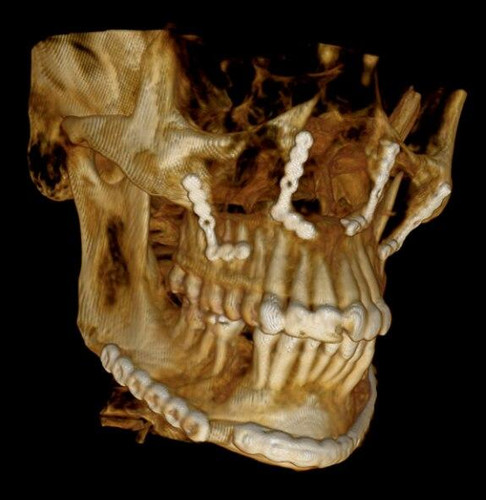

Introducing the CS 9300 Premium Panoramic, Cephalometric, and Cone Beam System from Carestream Dental – your ultimate solution for top-quality dental imaging. This state-of-the-art machine offers both 2D panoramic and cephalometric dental X-rays, as well as adjustable 3D cone beam images in up to seven different field of view sizes, extending up to 17x13.5 cm. This comprehensive range of imaging capabilities makes it a versatile tool, perfect for supporting a wide array of dental, surgical, or orthodontic examinations.

With the CS 9300 Premium, you can expect unparalleled image clarity and precision, allowing you to confidently diagnose and plan treatments with ease. Whether you're performing routine dental check-ups, complex surgical procedures, or orthodontic assessments, this system ensures outstanding results.

3D imaging:

- One-shot cephalometric

- Lateral

- Oblique

- Frontal (AP/PA)

- Submental-vertex

The CS 9300's 2D panoramic x-ray imaging capabilities are powered by variable focal trough technology, which provides optimal clarity for every image. The system's 3D imaging capabilities are based on cone beam technology, which delivers high-resolution images with a low radiation dose.

The CS 9300 is a versatile imaging system that can be used for a wide range of dental applications, including:

- Orthodontics

- Endodontics

- Implantology

- Oral and maxillofacial surgery

- TMJ disorders